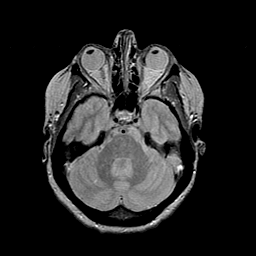

MR Study #2 -- Slice #17